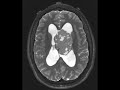

Ependymoma

These images demonstrate a heterogeneous mixed solid and cystic T1/T2 isointense lobulated lesion in the body of the left lateral ventricle extending through the foramen of Monro into the third ventricle in an adolescent patient. There are few areas of intralesional hemorrhage with blood-fluid levels best seen on the Sagittal T1 sequence. The mass is hypercellular as evidenced by restricted diffusion. Contrast was not administered on this study, but residual tumor on subsequent studies showed avid enhancement of the non-cystic portions. The differential diagnosis includes ependymoma, choroid plexus papilloma and carcinoma, central neurocytoma ,and subependymoma. On pathology, this lesion turned out to be an ependymoma. Approximately ⅓ of ependymomas are supratentorial and of these, less than half are intraventricular.